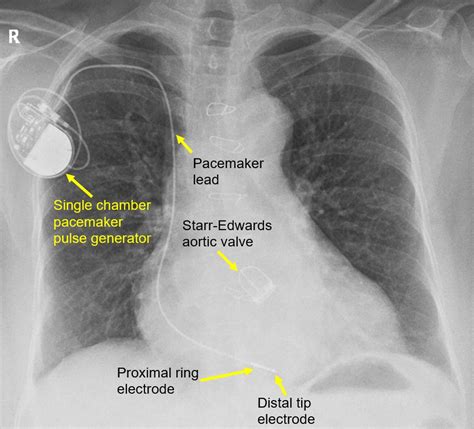

Both a Pacemaker en ICD are implanted under the skin, usually just below the collarbone. The procedure is typically minimally invasive, involving thin, flexible wires called leads that are threaded through a vein and into the chambers of the heart. The main unit, or generator, contains a battery and a computer circuit that monitors heart activity 247.